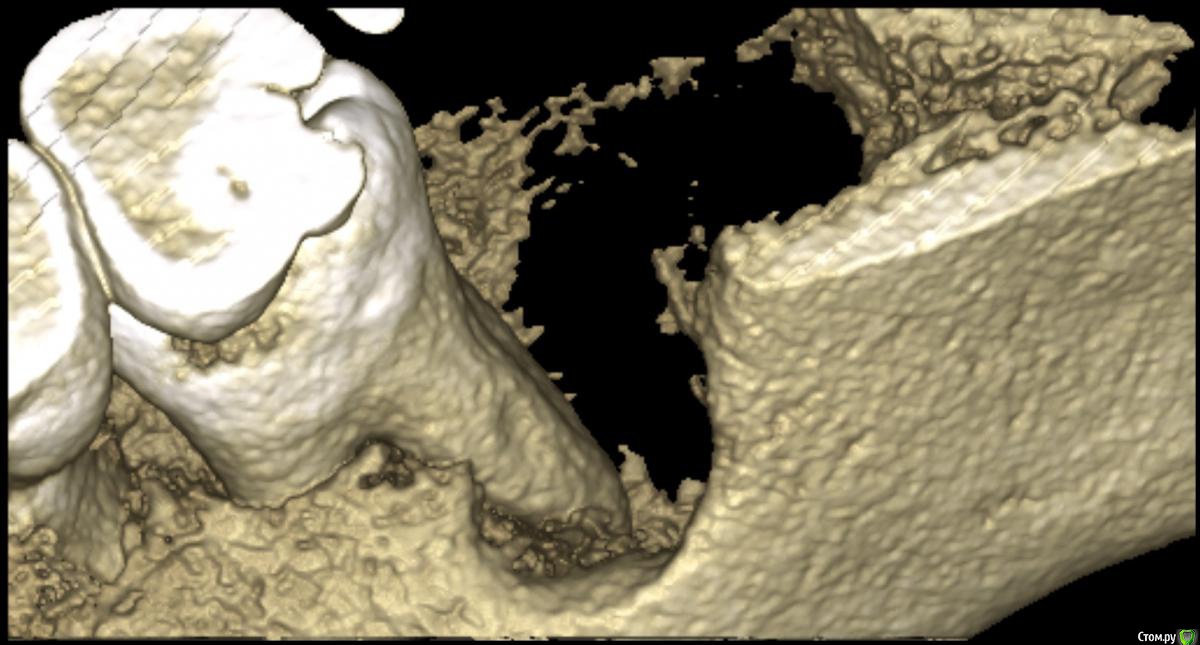

medbratec Опубликовано 12 октября, 2016 Автор Поделиться Опубликовано 12 октября, 2016 Был на консультации в частной клинике.Вердикт - семерку лучше пока не трогать, ее чувствительность обусловлена оголенными корнями. Проводить ревизию лунки, доставать осколок вежливо отказались, и отправляют с этим в челюстно-лицевую.Посоветовали сделать клкт для прояснения картины. Я сделал, однако повторную консультацию пришлось отложить. Не знаю как оттуда вытащить картинки. Если кому будет не лень, то оставлю ссылку на скачивание образа диска. (600мб)Рентгенолог сказал, что осколок в мягких тканях, причем с внутренней стороны, также обнаружилась кариозная полость в месте соприкосновения 7-го и 6-го зуба. Ссылка на комментарий

medbratec Опубликовано 13 октября, 2016 Автор Поделиться Опубликовано 13 октября, 2016 Я вас прекрасно понимаю. Был бы специалистом, то так сразу и сделал. Просто не знаю, что конкретно и под каким углом показывать. Сделал несколько скриншотов. Напишите, если они окажутся не слишком информативны. Ссылка на комментарий

medbratec Опубликовано 13 октября, 2016 Автор Поделиться Опубликовано 13 октября, 2016 Ссылка на комментарий

IvanK Опубликовано 14 октября, 2016 Поделиться Опубликовано 14 октября, 2016 скорее всего , это пломбировочный материал, лежит он не в костной ткани, а в мягких тканях, если не беспокоит, то можно не трогать 1 Ссылка на комментарий

red_butler Опубликовано 17 октября, 2016 Поделиться Опубликовано 17 октября, 2016 если это пломбировочный материал то на снимках "до" он должен быть, но я вижу там что то металлическое 2 Ссылка на комментарий

kramer Опубликовано 22 октября, 2016 Поделиться Опубликовано 22 октября, 2016 если это пломбировочный материал то на снимках "до" он должен быть, но я вижу там что то металлическоеЧисто по снимку похоже на кончик твердосплавного бора. ИМХО. Ссылка на комментарий

Kazankov.Egor Опубликовано 30 октября, 2016 Поделиться Опубликовано 30 октября, 2016 если это пломбировочный материал то на снимках "до" он должен быть, но я вижу там что то металлическоеИли комок йодоформа) Ссылка на комментарий